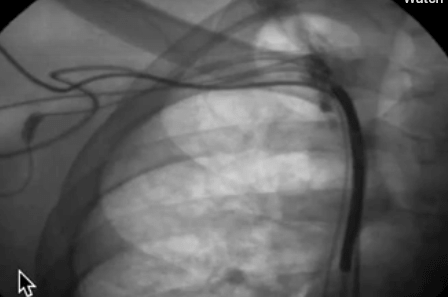

Persistent LSVC How to Implant Step by Step WITH audio 2018 D 23 Apr